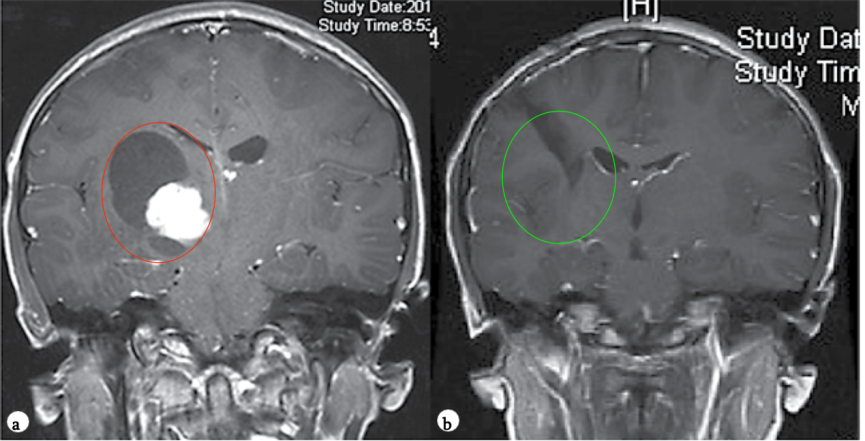

PA是儿童年龄组中常见的神经胶质瘤,它主要发生在幼儿(中位年龄为4岁)中。PA在后颅窝、视神经通路、背侧分叶状、外生性脑干肿瘤中所占比重较大,在t1加权像上通常表现为低张力囊性肿块,实性部分增强明亮(图1)。

图1。术前(a)和术后(b)颅脑磁共振MR,术前MR显示右侧丘脑较大囊实性占位,胶质瘤可能,皮质脊髓束(负责人体肢体运动的神经传导束)受压,脑室扩大,术后MR显示肿瘤全切,脑组织复位,无脑出血、脑水肿等损伤。